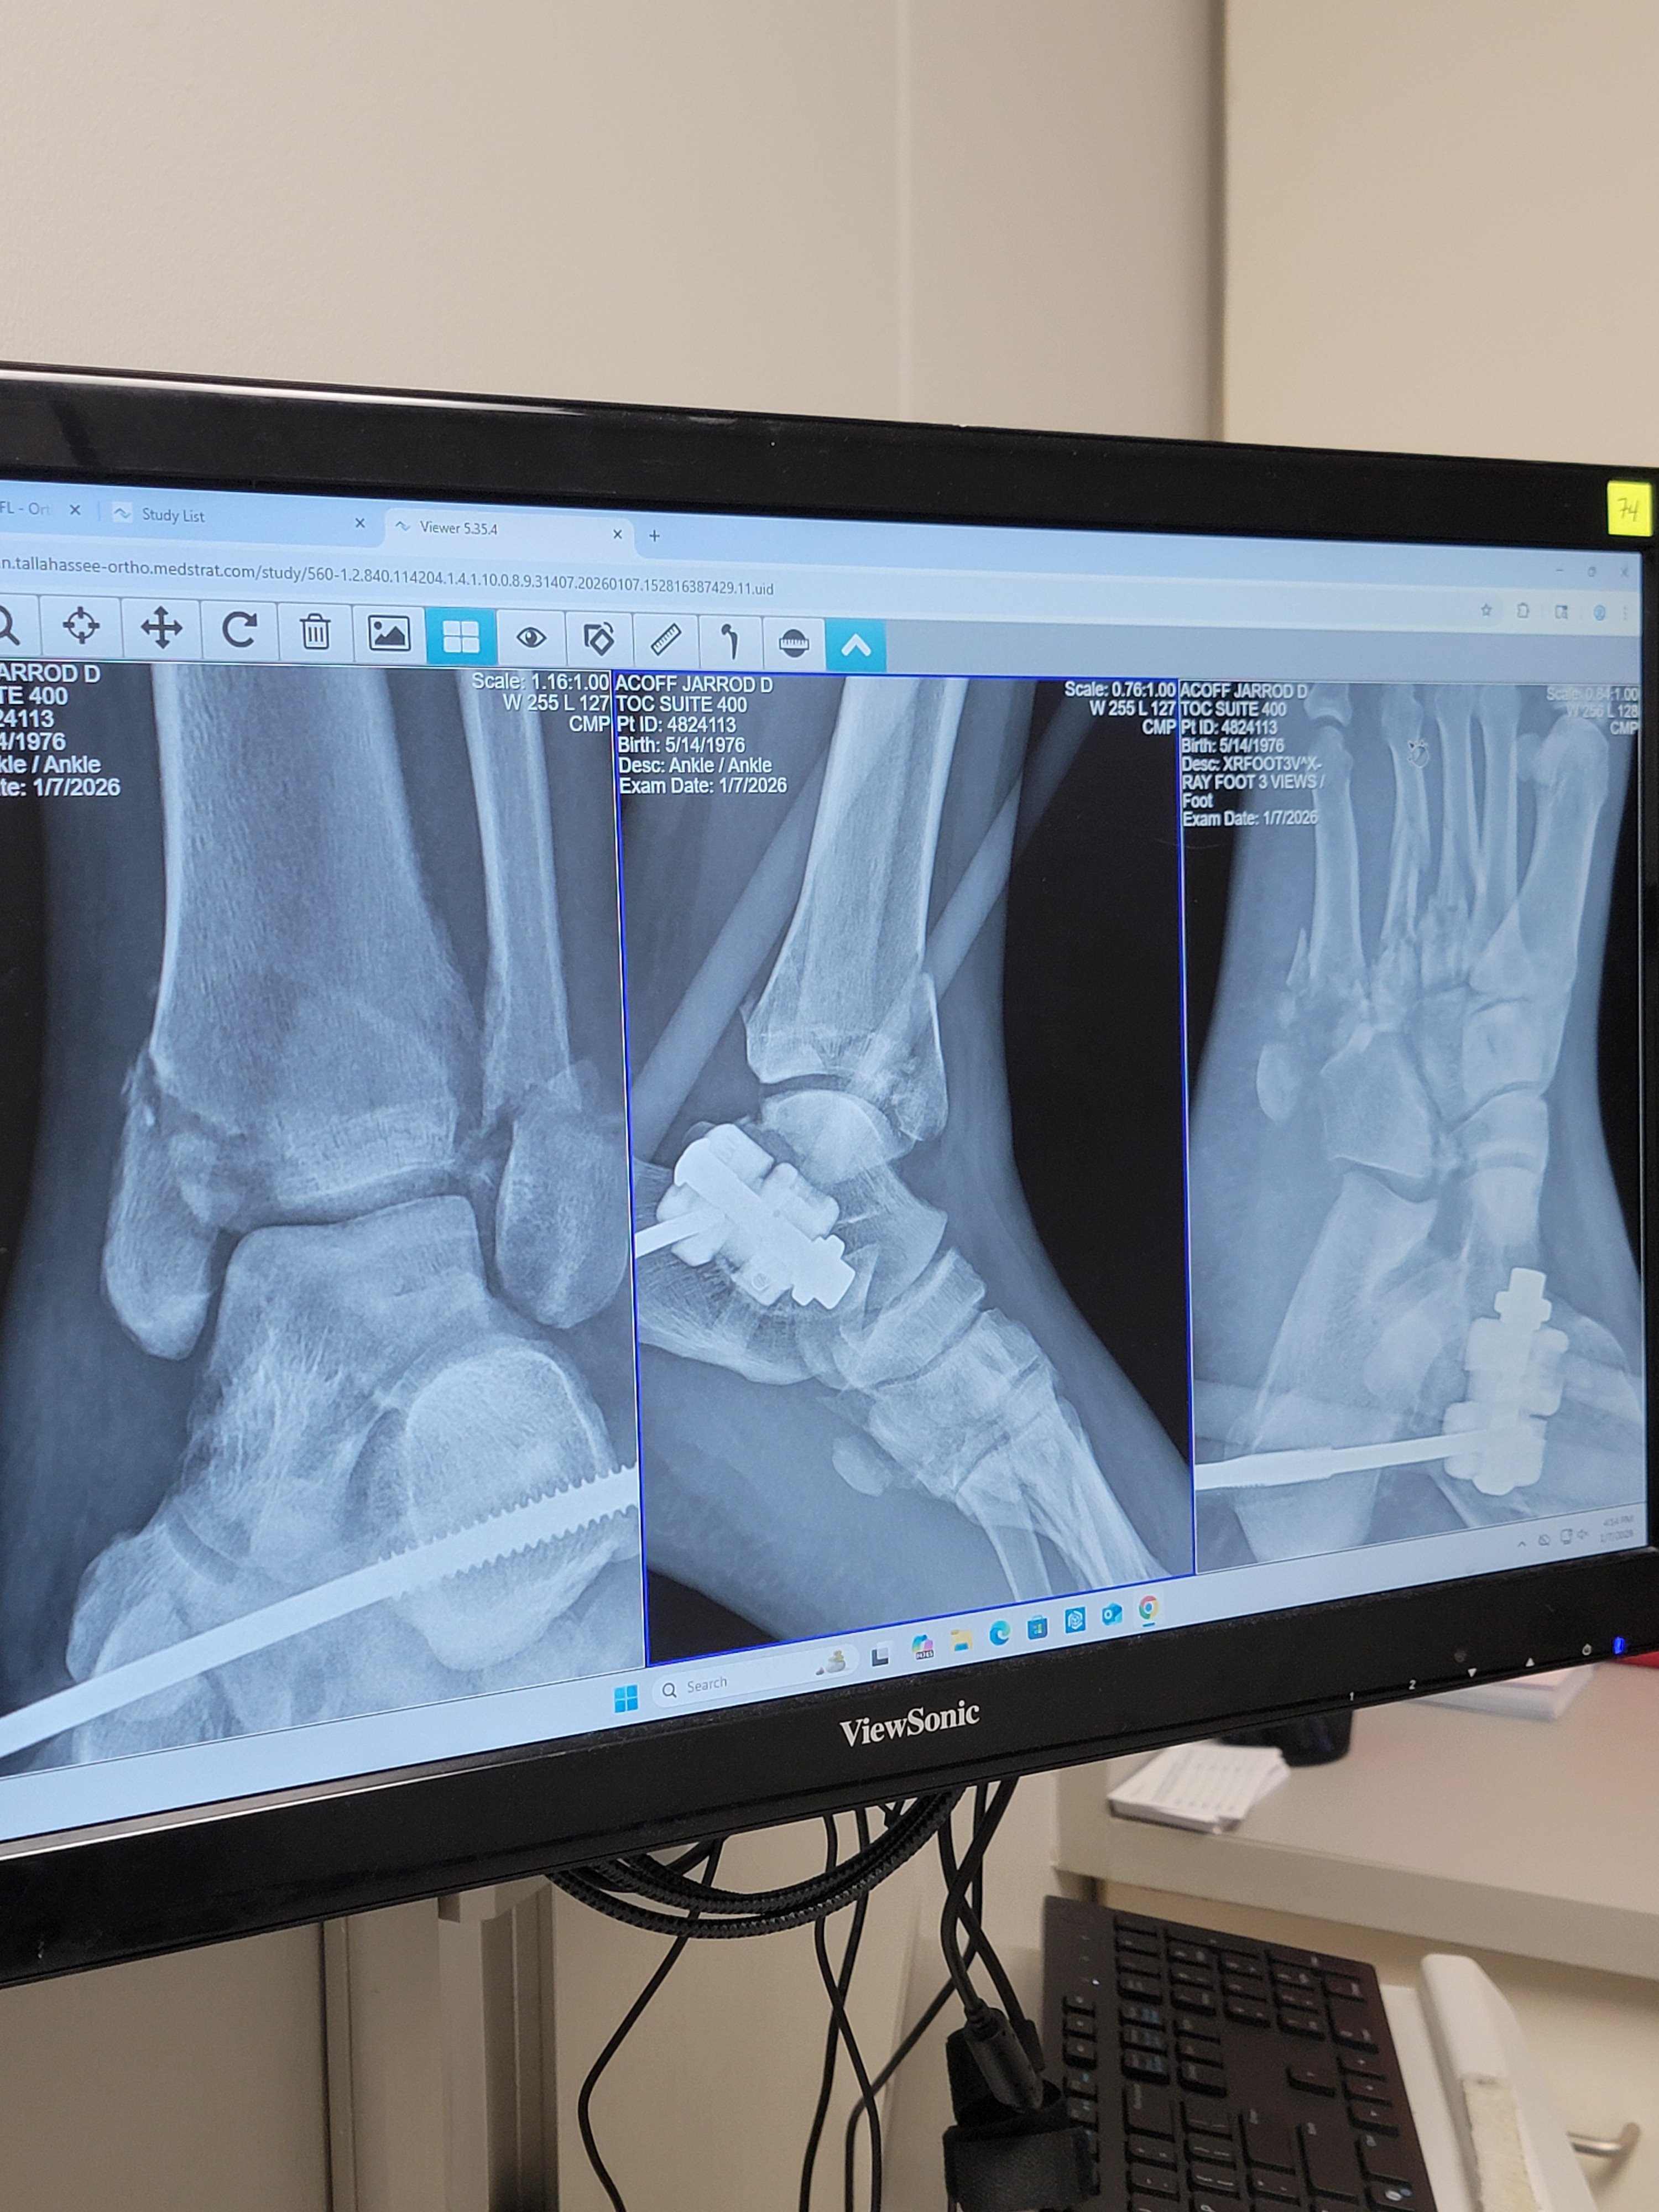

I suffered catastrophic damage to my left leg, including:

A fractured foot

A crushed ankle

Fractured tibia and fibula

I have already undergone one major surgery to repair my ankle and still need another surgery before I can begin to fully heal. Every day involves pain, limited mobility, and the emotional toll of not knowing how I will make it through this financially.